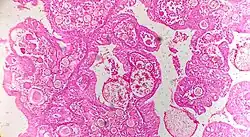

![]() |

Follicular lymphoma | Micrograph showing a small B-cell lymphoma compatible with follicular lymphoma. H&E stain. | Category: Histopathology of follicular lymphoma | Follicular lymphoma |